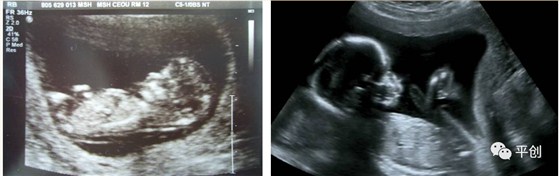

更準(zhǔn)確的醫(yī)學(xué)診斷,來自B超檢查結(jié)果的輔助,準(zhǔn)確的B超檢查結(jié)果,來自B超醫(yī)生看到的B超圖像,清晰的B超成像,來自好的耦合劑。所以說,好的耦合劑對B超的成像很重要。

而影響B(tài)超檢查成像的因素有兩點,一是來自好的探頭,二是來自優(yōu)質(zhì)的耦合劑。如果這兩個產(chǎn)品其中有一個質(zhì)量不過關(guān),即對B超成像有一定程度的影響,可能會有成像不清楚,醫(yī)生無法準(zhǔn)確判斷所檢查器官的實際病變,嚴(yán)重的有可能度至醫(yī)生誤診的后果。

普通的卡波姆,其透聲力沒達(dá)到超聲波傳導(dǎo)的系數(shù),無法有效地傳達(dá)聲波,同時沒有良好的偶合功能,這種情況下,就無法形成清晰的圖像。

另外,有的廠家的耦合劑濃度太高,或是太稀,涂在檢查部位上,馬上就有一部分水流出,讓患者感到很不舒服,而過稀的耦合劑會減低其偶合性,過濃的耦合劑難以展開涂抺,或涂抺不均勻,影響探頭在檢查部位的滑動,這兩種情況都會減低B超中的耦合性,影響B(tài)超成像的清晰度,從而影響醫(yī)生看到的結(jié)果而給出錯誤的判斷,甚至間接的引發(fā)了醫(yī)療事故,嚴(yán)重地影響了醫(yī)院的專業(yè)度和信服力。這些都是醫(yī)生和醫(yī)院及患者都不希望發(fā)生的。

所生產(chǎn)出來的耦合劑無雜質(zhì)、透明度高、不易干,不化水,易偶合、易擦凈,透聲性超過國家標(biāo)準(zhǔn)的50%(數(shù)據(jù)通過國家指定的第三方檢測機(jī)構(gòu)檢測結(jié)果所得),完全地解決了成像不清晰的難題。